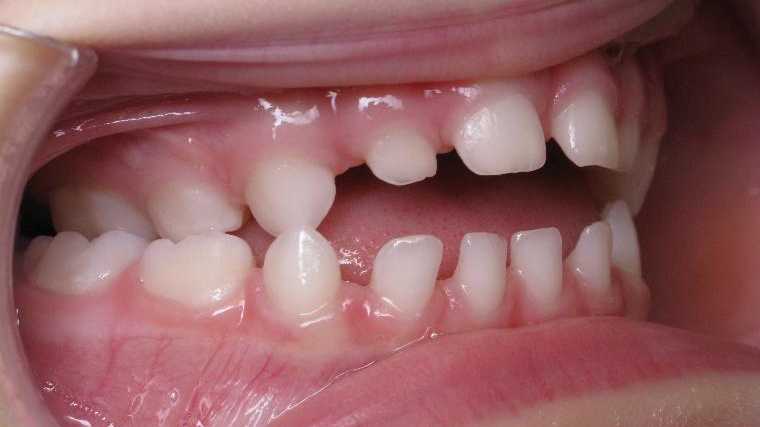

12 béance inversé droit 4 ans

inversion postérieur coté droit et espace entre les dents du haut et du bas (diastèmes)